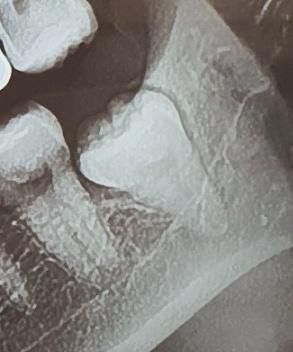

안 올라온 사랑니 발치해야하나요??

사랑니가 저상태인데 발치해야하나요?

더이상 올라오진 않는건지 1년동안 그대로인데..

한번씩 잇몸이 붓고 아프다가 가라앉고를

반복하는데 병원가야하나요..

• 1번 째 사진

해당 사랑니로 인해서 한번씩 붓고 통증이 있는 경우라면 사랑니를 발치 하시는 것이 좋겠습니다.

사랑니가 잇몸 안에 있고 문제를 발생시키지 않는다면 발치를 하지 않아도 됩니다. 크게 문제가 되진 않을 것으로 생각되나 자세한 확인을 위해서 치과에서 진료를 받아보는 것을 권유드립니다.

별 문제가 없다면 그냥 두셔도 되지만 반복적으로 염증이 생긴다면 발치를 하시는걸 추천드립니다.

해당치아는 완전 매복 사랑니이고 크게 불편함이 없다면 그냥 두어도 되지만 잇몸 염증을 유발한다면 발치를 고려해보세요